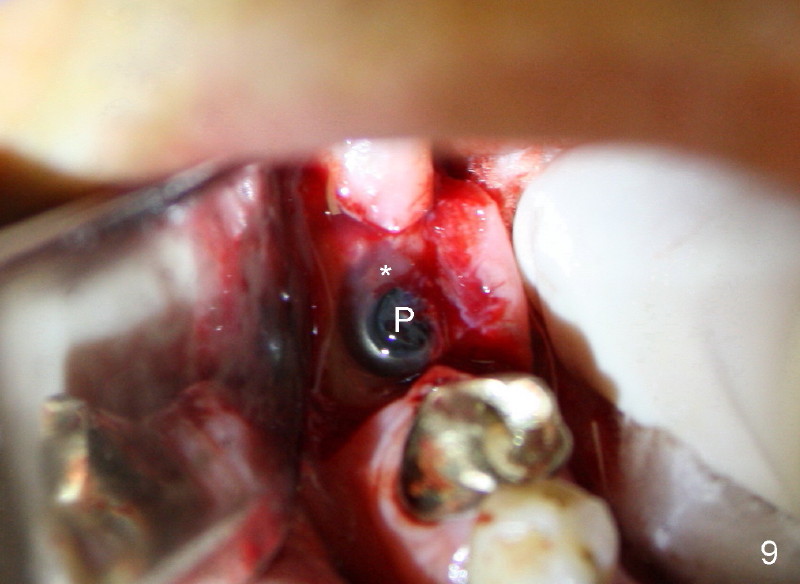

Unfortunately, there is bone resorption around the implant 3 months postop (Fig.6: >, as compared to Fig.4). Granulation tissue is present over the implant (Fig.7 *). The patient complains occasional pain and swelling after implant placement. Bone resorption is confirmed after removal of granulation tissue around the implant (Fig.8 *). After acid etch, Endogain (Fig.9 *, Straumann) is placed around the implant (P: healing plug). Flaps are approximated with 4-0 plain gut suture. Collagen membrane should have been used. Amoxicillin is prescribed, but the patient does not take it. It appears that bone graft to the sockets of #19 helps form an apparently continuous bone plate at the alveolar crest over the mesial (M in Fig.6') and distal (D) sockets, as compared to Fig.4'.